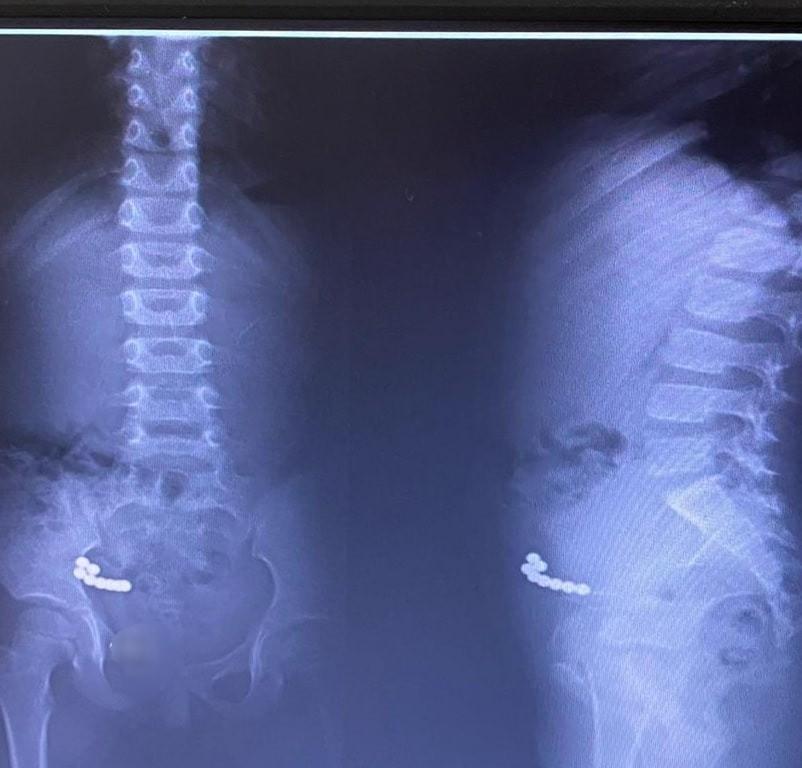

Магнитные шарики на рентгене: Интересные находки

Раздел: Картинки на заметку